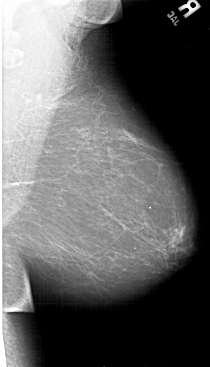

A_1492_1.RIGHT_MLO

RIGHT_MLO LINES 6601 PIXELS_PER_LINE 3766 BITS_PER_PIXEL 12 RESOLUTION 43.5 NON_OVERLAY

FILE: A_1492_1.LEFT_CC.OVERLAY

TOTAL_ABNORMALITIES 1

ABNORMALITY 1

LESION_TYPE CALCIFICATION TYPE PUNCTATE DISTRIBUTION CLUSTERED

ASSESSMENT 4

SUBTLETY 3

PATHOLOGY BENIGN

TOTAL_OUTLINES 1

BOUNDARY